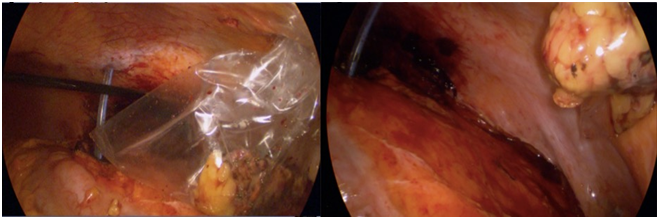

A 72 years old man was diagnosed with a small left renal mass incidentally during an ultrasonography for to an aortic abdominal aneurysm. A computer tomography (CT) scan confirm an exophytic 3cm left renal mass; therefore, an unclamped-laparoscopic partial nephrectomy was performed without difficulty. The tumor was placed inside of a plastic self-performed thermofused retrieval bag (Figure 1) and extracted trough a 12mm laparoscopic port. Finally, a drain was also placed close to the renorrhaphy. The patient was taken to the hospital room and in that moment, we realized that the bag was broken and the tumor was not inside. With the patient and family consent, a CT scan was performed showing a small mass next to the renorrhaphy (Figure 2); therefore, we decided to underwent an exploratory laparoscopy using the same port and patient position. Once laparoscopic camera was introduced, the tumor was found over the sigmoid colon slightly adhered (Figure 3) and extracted inside of a surgical glove. The hospital stay was 3 days with no perioperatory complications and the final histopathological finding was a 2cm cromophobo renal cell carcinoma with negative surgical margins.

Figure 1 Left: Plastic self-performed retrieval bag with the tumor inside. Right: broken bag at the time of tumor extraction.